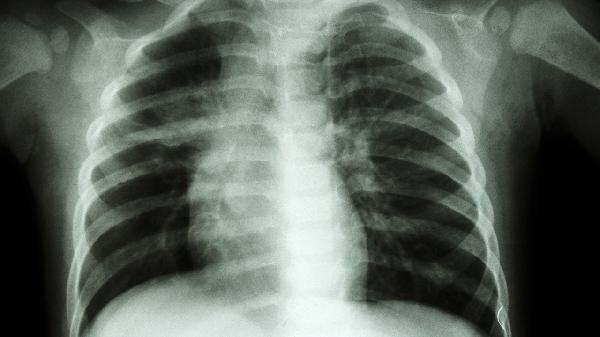

肺炎、胸膜炎等疾病可能在体力消耗后诱发胸痛,多伴有咳嗽、发热等症状。需完善胸部CT等检查,医生可能开具左氧氟沙星片、氨溴索口服溶液或布地奈德福莫特罗粉吸入剂等药物治疗。保持室内空气流通,避免呼吸道感染加重病情。